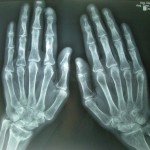

Image of the month-Jan 2014

Whats the diagnosis in this case?